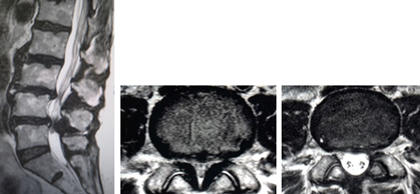

(左、中)術前のMRIでは特に第4/5椎間で脊柱管の高度な狭窄を認めています。

(右)棘突起縦割式椎弓形成(切除)術を施行し、脊柱管は著明に拡大し神経症状の改善を認めています。